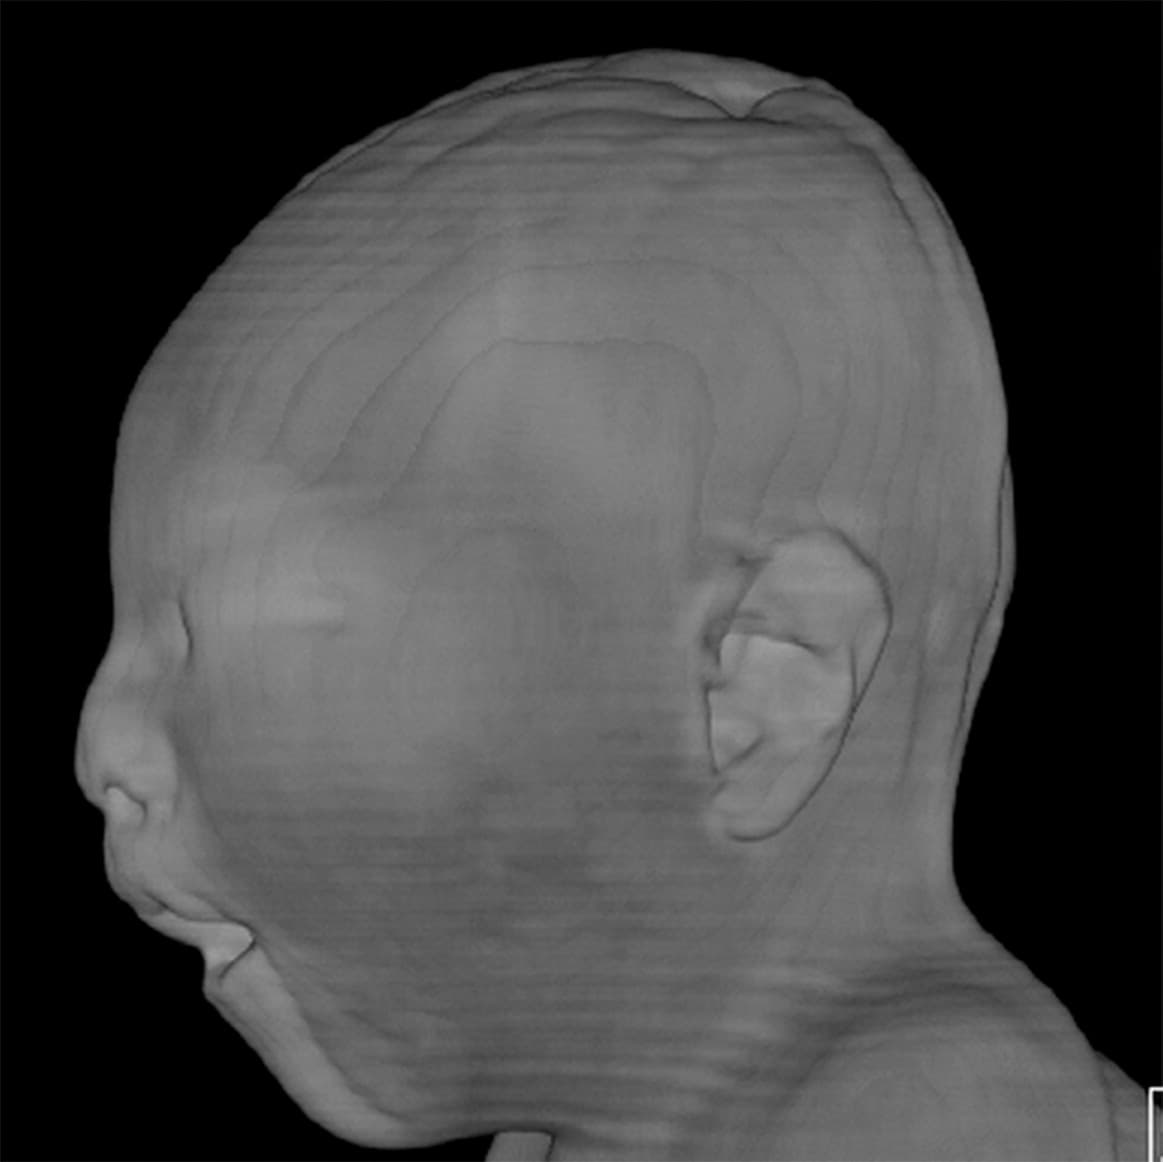

El zika y el cerebro de una bebé de una madre de 18 años

Un estudio en Brasil muestra cómo el virus del Zika ataca y destruye parte del cerebro de los bebés.

A las 12 semanas de embarazo, esta madre de 18 años tuvo una erupción en la piel. Su infección de zika fue confirmada en el Instituto de Pesquisa de Campina Grande, en Brasil.